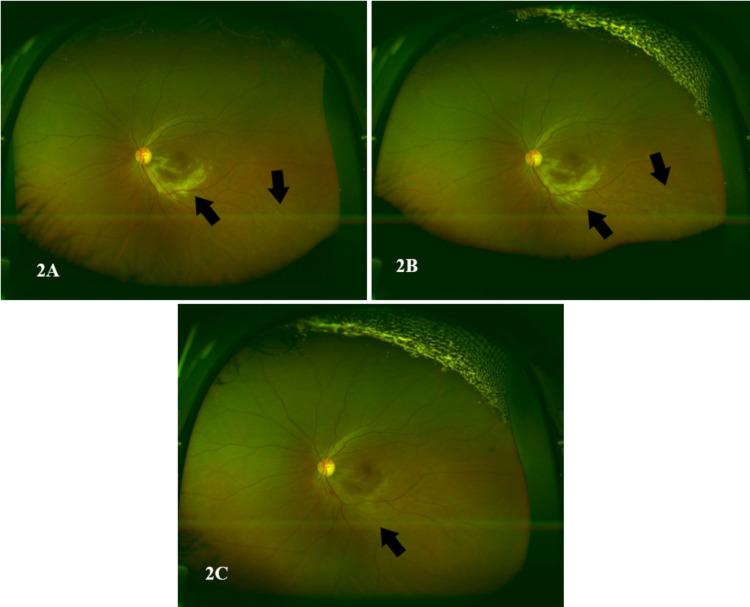

The purpose of this case report was to present a case of cytomegalovirus (CMV) retinitis in a patient with diffuse large B-cell lymphoma (DLBCL) post-CD19 chimeric antigen receptor (CAR) T-cell therapy. A 43-year-old female patient who was complaining of metamorphopsia and sudden blurring in the vision of her left eye was referred to the ophthalmology department. The patient had DLBCL and was started on systemic chemotherapy, which showed no response to therapy and disease progression. Therefore, she was diagnosed with primary refractory DLBCL and treated with CAR T-cell therapy. The visual acuity of the left eye was 20/25 in the left eye on the Snellen visual acuity chart. The dilated fundus examination of the left eye demonstrated a diffuse yellowish retinal infiltration radiating from the optic disc involving the inferior macula and inferotemporal arcade. A color fundus image of the left eye showed a creamy infiltrate involving the inferior half of the macula sparing the fovea with subtle small white lesions in the midperiphery. Horizontal cross-section optical coherence tomography (OCT) of the macula of the left eye showed islands of destruction of all the retinal layers, which are replaced with moderately hyperreflective material; these infiltrates spare the fovea but with subfoveal fluid. Further systemic evaluation indicated CMV viremia reactivation and an absolute CD4+ cells count of 13 cells/mcL. Thus, she was diagnosed with CMV retinitis. After three days of the initial presentation, she received the first intravitreal ganciclovir injection; 17 days after presentation, she received five intravitreal ganciclovir injections. The patient responded well to intravitreal ganciclovir therapy. She regained very good vision, and the visual acuity was 20/20 in both eyes. Early recognition and initiation of proper treatment are crucial. Thus, any visual complaints in patients with immunodeficiency should be taken seriously and should be further assessed. As the right eye had retinal scaring indicating previous retinitis, prophylactic treatment with ganciclovir could have been used to reduce the risk of retinitis development in the left eye.

本病例报告的目的是介绍1例接受CD19嵌合抗原受体(CAR)T细胞治疗的弥漫性大B细胞淋巴瘤(DLBCL)患者发生巨细胞病毒(CMV)视网膜炎的情况。一名43岁女性患者因主诉视物变形及左眼视力突然模糊而被转诊至眼科。该患者患有DLBCL,开始接受全身化疗,但治疗无反应且疾病进展。因此,她被诊断为原发性难治性DLBCL并接受CAR T细胞治疗。在斯内伦视力表上,该患者左眼视力为20/25。左眼散瞳眼底检查显示,从视盘发出的弥漫性淡黄色视网膜浸润累及黄斑下及颞下弓。左眼彩色眼底图像显示,黄斑下半部有奶油状浸润,中央凹未受累,周边中部有细微的小白斑。左眼黄斑水平截面光学相干断层扫描(OCT)显示,所有视网膜层均有破坏区,被中等高反射物质取代;这些浸润灶未累及中央凹,但有黄斑下液。进一步的全身评估显示CMV病毒血症再激活,绝对CD4+细胞计数为13个/微升。因此,她被诊断为CMV视网膜炎。首次就诊3天后,她接受了首次玻璃体内更昔洛韦注射;就诊17天后,她接受了5次玻璃体内更昔洛韦注射。该患者对玻璃体内更昔洛韦治疗反应良好。她恢复了很好的视力,双眼视力均为20/20。早期识别并开始适当治疗至关重要。因此,免疫缺陷患者的任何视觉主诉都应予以重视并进一步评估。由于右眼有视网膜瘢痕提示既往有视网膜炎,可使用更昔洛韦进行预防性治疗以降低左眼发生视网膜炎的风险。